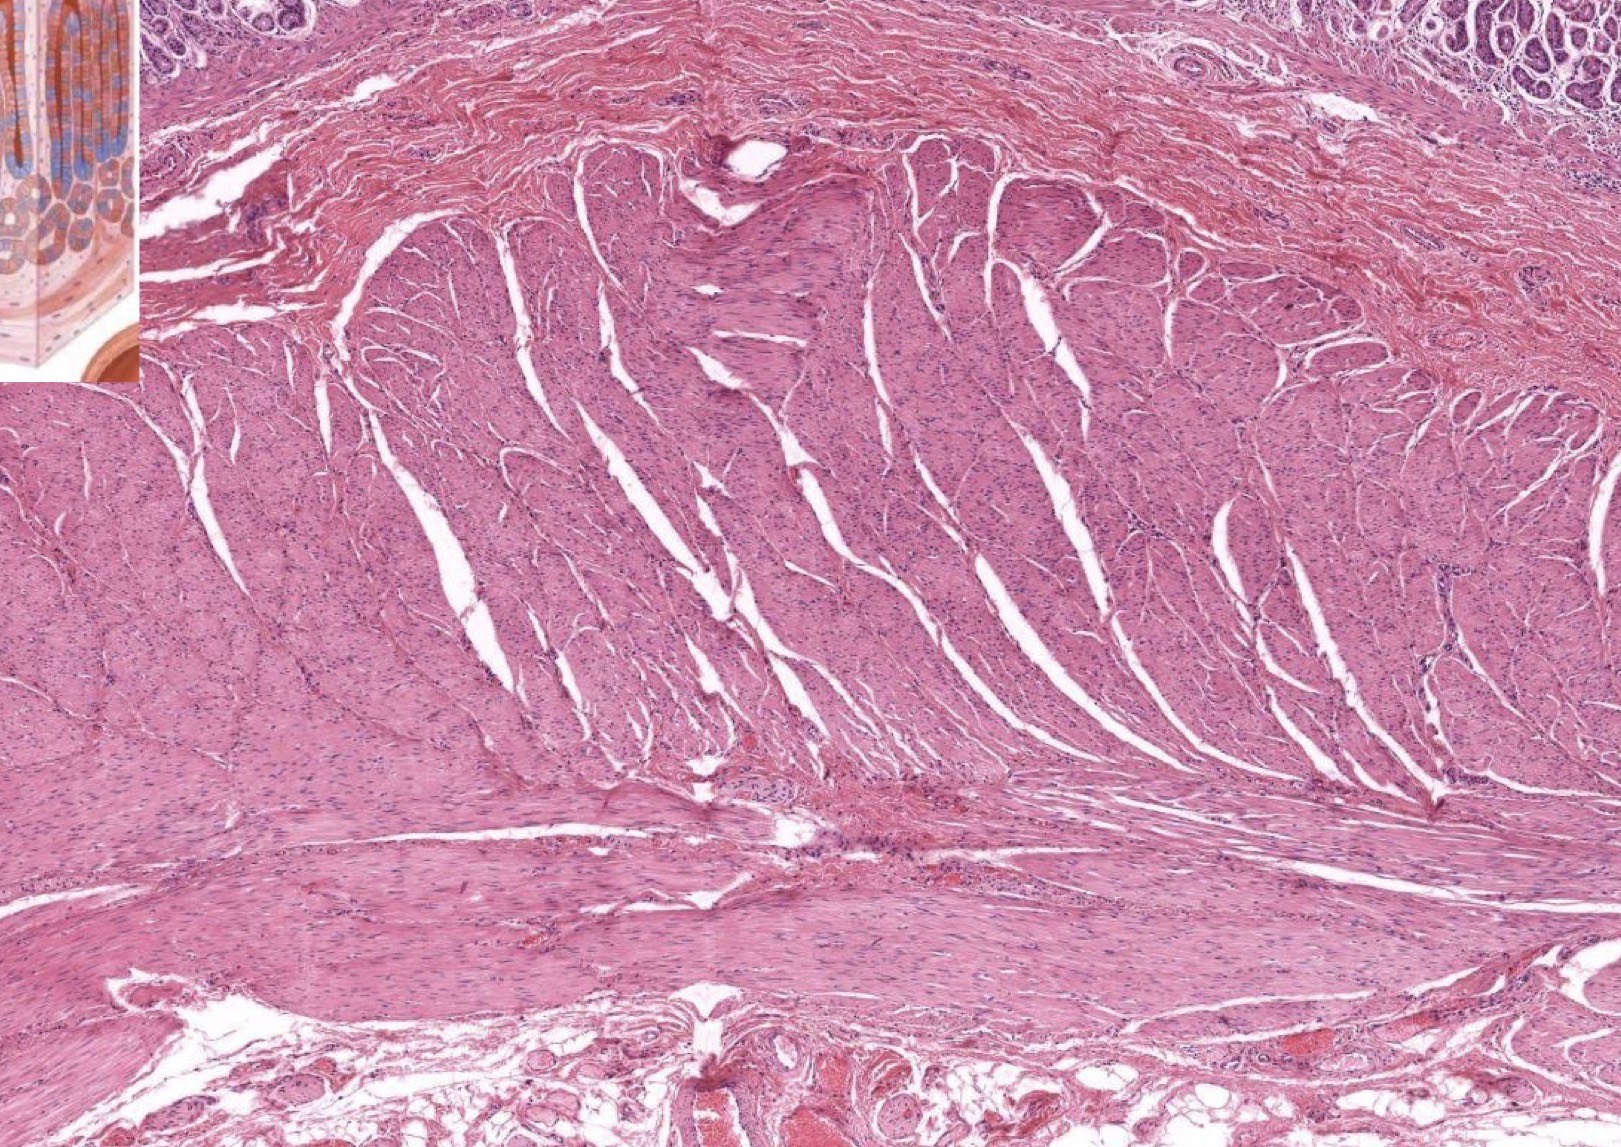

Identify the Layers and Where?

Purple and 1 pink below = Mu, DICT = Sm, Smooth M = Me, Unilocular Adipose = Ad. This is Stomach, Fundus because less GP and more G.

Purple and 1 pink below (Mm) = Mu (Parietal cells here), DICT = Sm. This is Stomach, Fundus because less GP and more G.

Mm and Sm. This is Stomach.

DICT = Sm, Smooth M = Me, Unilocular Adipose = Ad. This is Stomach.